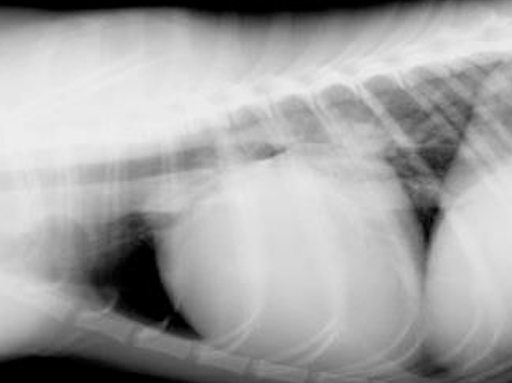

Radiography

- ์ฒ์์ ๋จผ์ LA, LV ํ์ฅ(enlargement)๋ถํฐ ๋ฐ์

- R-L shunt ๊ทผ์ฒ๊น์ง ๋ณ์ด ์งํ๋๋ฉด dAo & mPA ํ์ฅ

- Aorta์ ๋นํด ์๋์ ์ผ๋ก ๋ฒฝ์ด ๋ ๋๊บผ์ด mPA ๊ฐ ๊ฝ๋ฆฌ ๋ชจ์์ผ๋ก enlarged๋จ